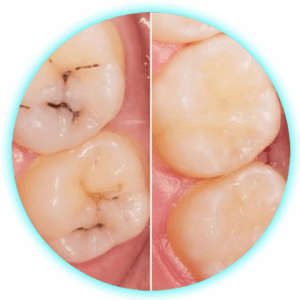

Restauraciones Complejas

$30,00 -

Restauraciones Compuestas

$25,00 -

Restauraciones Simples

$20,00 -

Sellantes de Fosas y Fisuras

$15,00